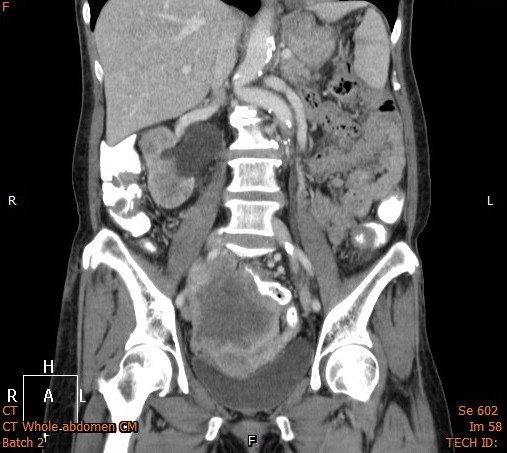

Answer : B. Abdominal/Pelvic mass

• Occasionally masses of the pelvis are visible on an abdominal X-ray.

• If large, masses of the pelvis may extend into the abdomen and displace bowel.

• Investigation with ultrasound and/or CT is required for assessment of a suspected abdominal mass.

Key points : Pelvic masses can displace bowel upwards

Abdominal CT images